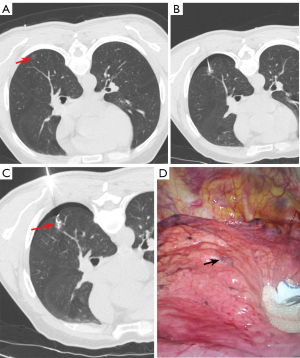

In the conventional coil group, an 18G needle was advanced along the planned needle path into the lung parenchyma. Needle tip placement was verified and adjusted as needed with repeated CT scans. Once the needle tip was positioned within 10 mm of the PN, the coil was inserted through the needle and partially deployed within the parenchyma depending on the depth of PN. Finally, the needle was withdrawn smoothly, and the remaining portion of the coil was left above the pleura (Figure 2).

In novel coil group, a 20 G needle was employed following the same puncture technique as in the conventional coil group. The length of the coil tail was selected according to the depth of PN. When the needle tip was positioned within 10 mm of the PN, a pusher was used to deploy the coil into the lung parenchyma. Finally, the needle was withdrawn smoothly, ensuring the coil tail extended outside the pleura (Figure 3).